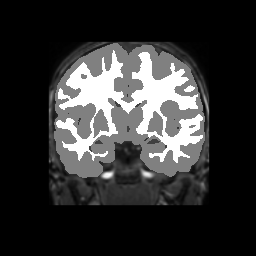

Accuracy is reported as Dice overlaps between a tool's segmentation and the Internet Brain Segmentation Repository (IBSR) manual segmentation for each of the 18 IBSR subjects. The inter-tool comparison (on the left below) shows the median Dice coefficient for each tissue class. The overlaps for FSL (from which the median values are drawn) are shown in the plot on the right.

Subject Accuracy (IBSR)

Overlap coefficients for each tissue class are shown here for each IBSR subject. Select a subject below to see the FSL results compared to other tools.